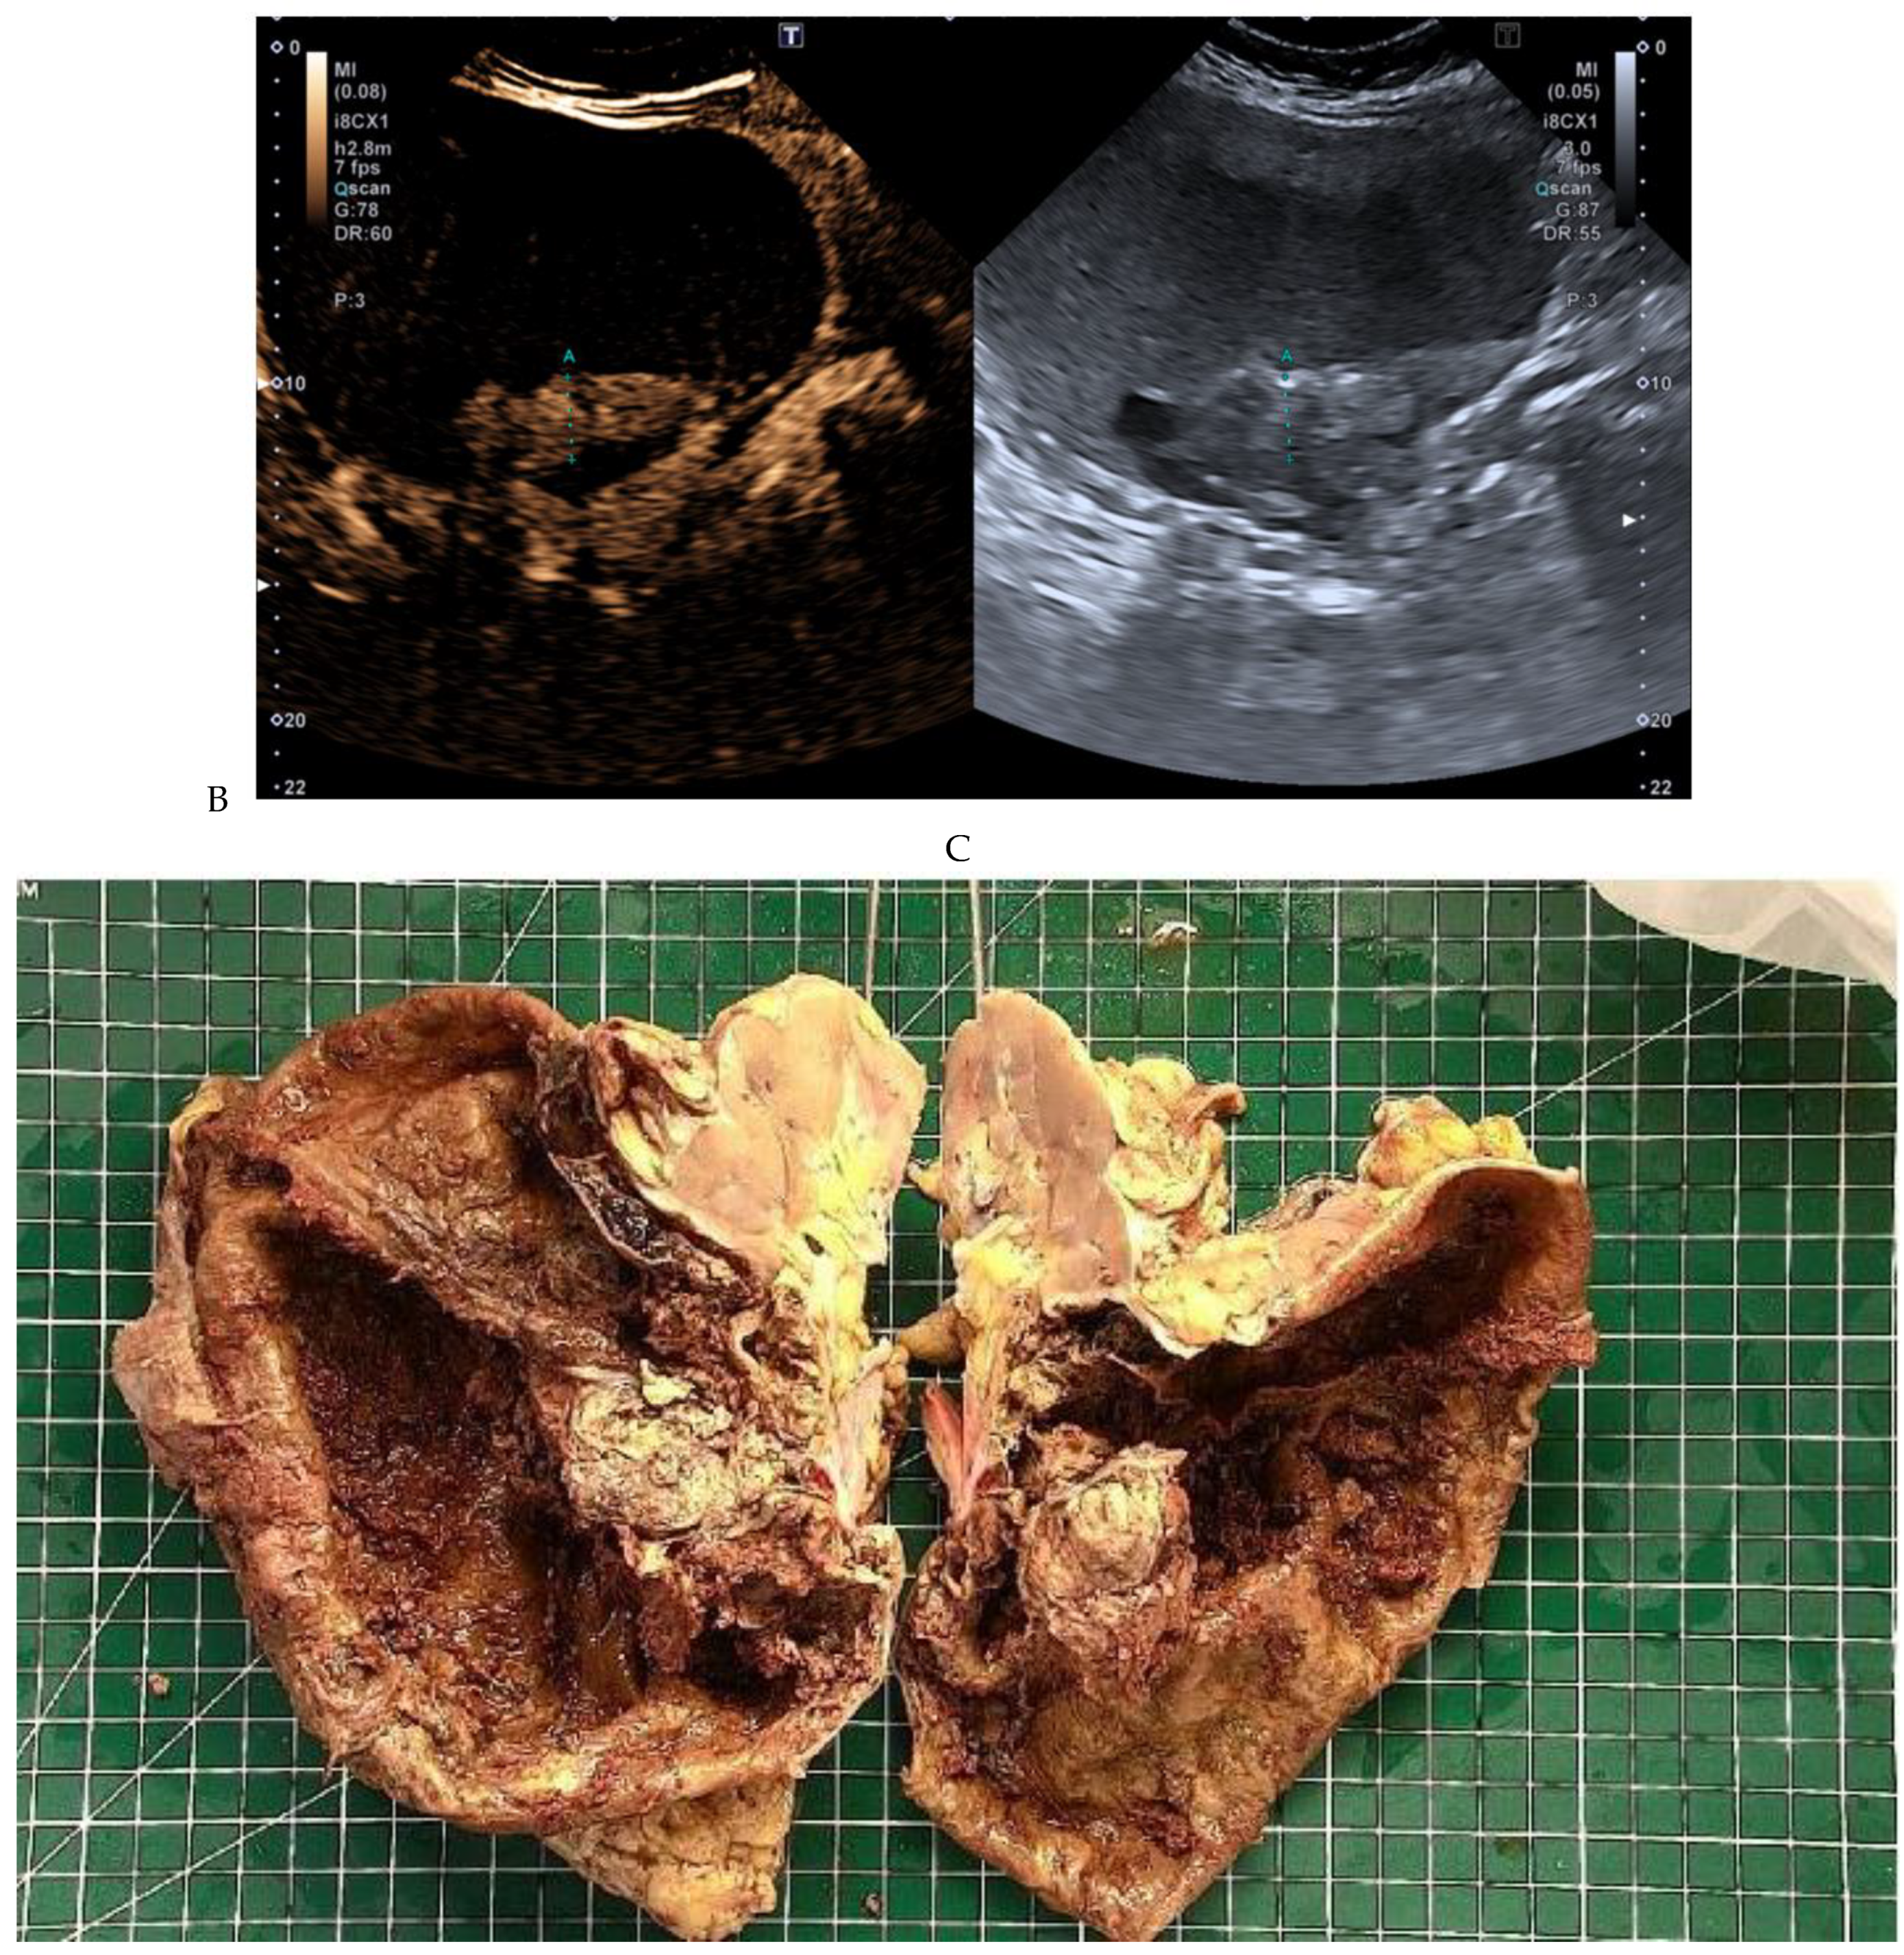

Figure 2.

Oncocytoma in the right kidney of a 42-year-old man. (A) On the unenhanced image, the 4.8 cm lesion is isodense relative to the renal parenchyma. Enhancement is seen on the corticomedullary phase image (B), followed by washout on the nephrographic (C) and excretory (D) phase images. (E) Macroscopic view of the lesion after radical nephrectomy. Courtesy of Pr S. Ferlicot, Department of Pathology, Bicêtre.

Figure 4.

Multiphasic CT enhancement of a papillary renal cell carcinoma in the middle part of the right kidney of a 63-year-old woman. (A) Mean unenhanced attenuation was 35 HU. (B) Mean corticomedullary phase attenuation was 45 HU. (C) Mean nephrographic phase attenuation was 59 HU. (D) Mean excretory phase attenuation was 65 HU.